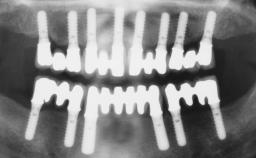

A healthy 31-year-old female patient presented with a failing maxillary left lateral incisor crown. The crown regularly loosened, and the remaining tooth was neither restorable nor rational to treat. The patient had a high smile line, a medium soft tissue biotype with a compromised mesial papilla (shorter than the contralateral one), and a horizontal scar in the buccal soft tissue as a result of past periapical surgery.

| Timing of placement | Immediate Placement (extraction sockets) (Type I) |

| Socket walls | Intact |

| Thickness of buccal wall | less than 2 mm |

| Anticipated residual defect after implant placement | 2 mm or less |